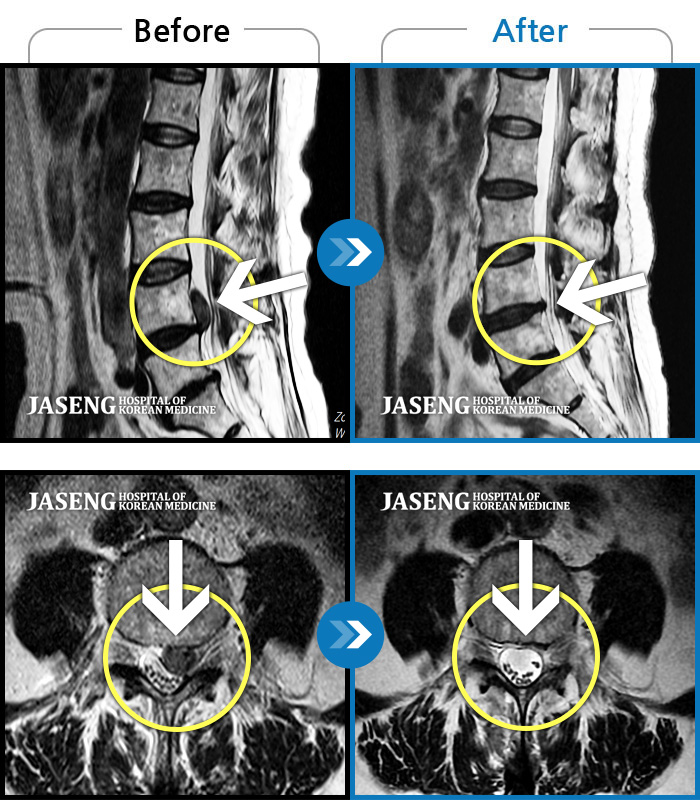

Before

After

환자에게 사전 동의를 받아 동일 조건에서 촬영되었습니다.

개인에 따라 치료 후 부작용이 발생할 수 있으니 의료진과 상담 후 치료를 진행하시기 바랍니다.